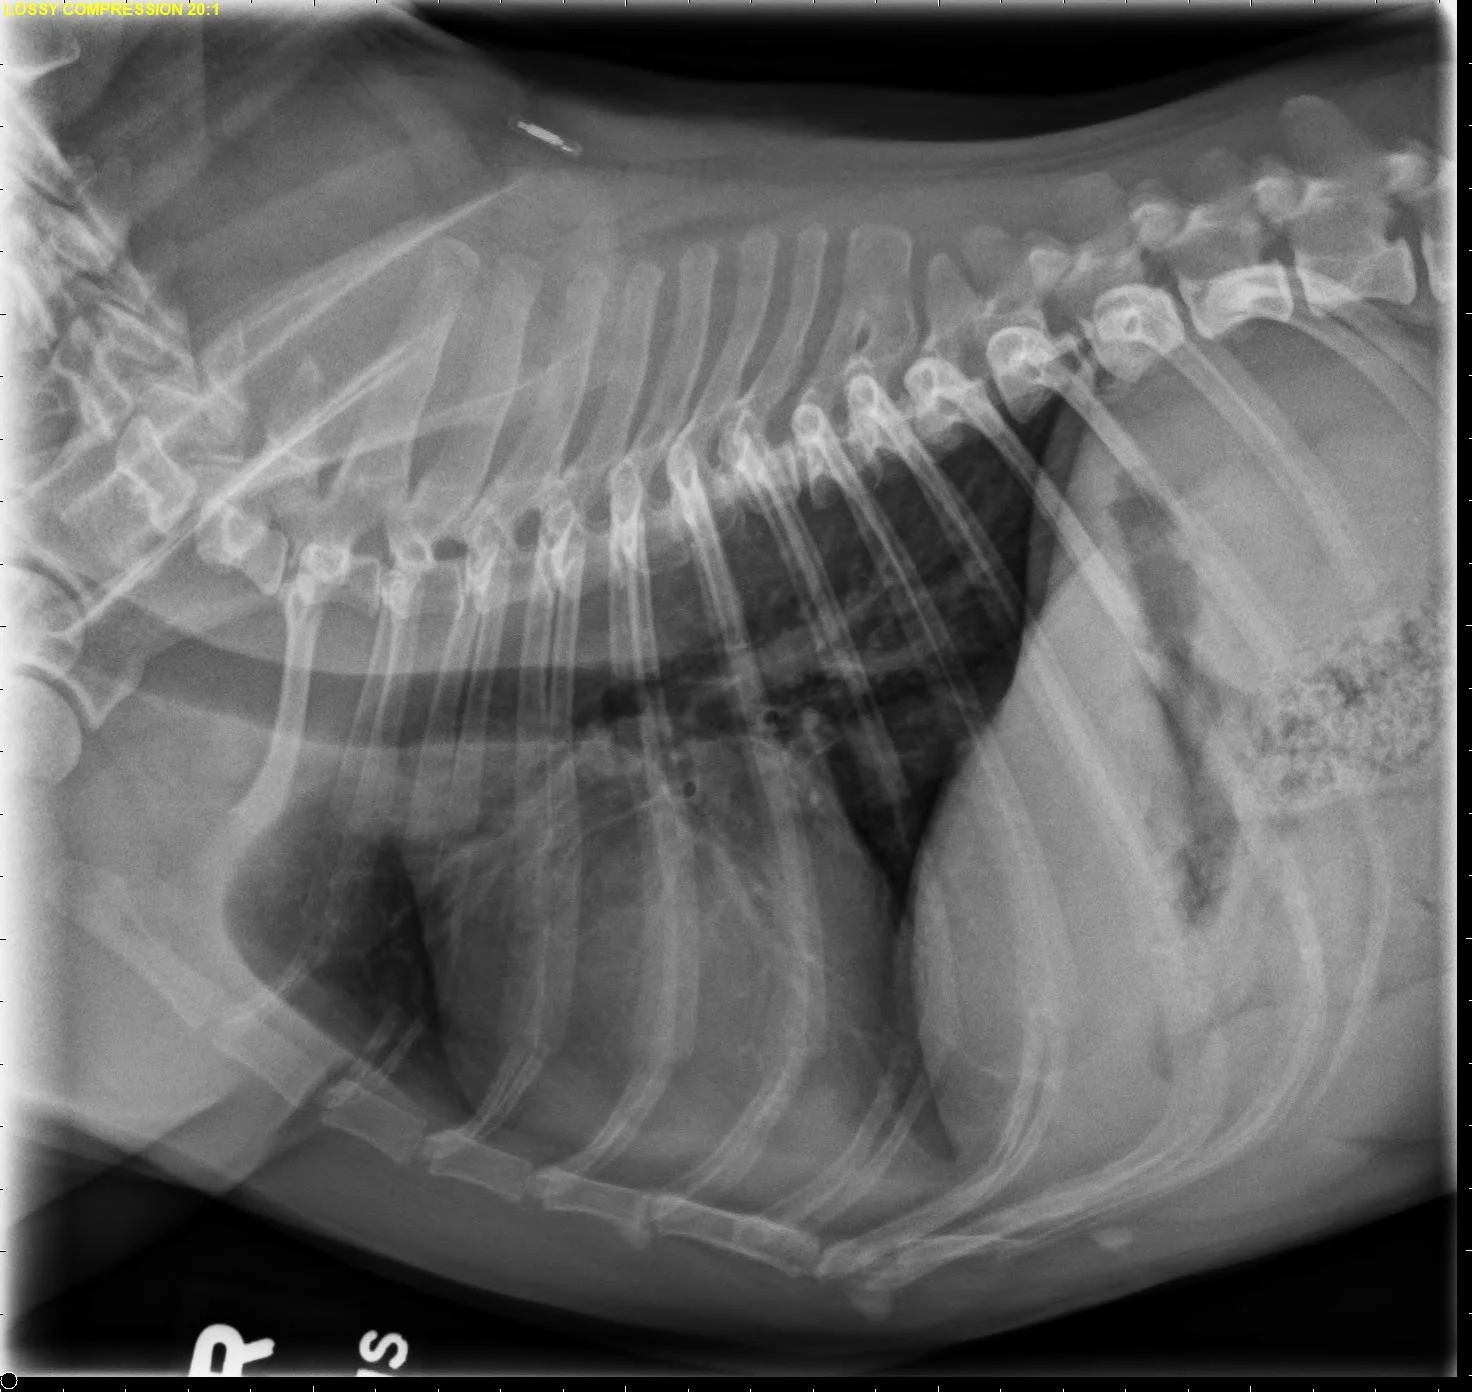

At least 2 orthogonal views, ideally taken during peak inspiration, are necessary for appropriate radiographic study of the cardiovascular system; however, a 3-view study is ideal for comprehensive evaluation of the thorax. Some differences should be considered when deciding to acquire a right versus left lateral projection and a dorsoventral (DV) versus ventrodorsal (VD) projection. On the left lateral view, the cardiac silhouette is typically more rounded and the apex is further elevated from the sternum than in the right lateral view (Figure 1). In the DV view, the cardiac silhouette is commonly displaced cranially and to the left by the diaphragm and appears more rounded than in the VD view. The caudal pulmonary vasculature is better delineated in the DV view, whereas the lung field (particularly the accessory lobe) is better evaluated in the VD view (Figure 2).

FIGURE 1 Normal right and left lateral projections of the thorax in a large, crossbreed dog. The difference in the cardiac silhouette and the apex elevation (arrow) from the sternum in the left lateral view can be seen. VHS, VLAS, modified VLAS (M-VLAS), and VRHi collected from the right lateral view are 10.6, 1.7, 2.8, and 3, respectively, and 10.6, 1.5, 2.9, and 3.4, respectively, collected from the left lateral view. Given these differences, serial radiography should be performed using the same lateral view if only one view is used. In some dogs, roundness of the cardiac silhouette in the left lateral view can be pronounced and misinterpreted as right-sided heart enlargement, particularly if compared with a prior right lateral view. Images courtesy of Federico Villaplana Grosso, DACVR, DECVR